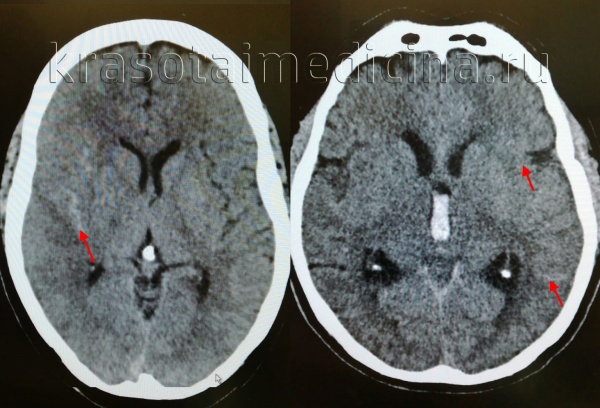

(а) Бесконтрастная КТ, аксиальный срез: в нескольких бороздах и в межножковой цистернах определяется скопление гиперденсной крови вследствие травматического субархноидального кровоизлияния (тСАК).

(б) MPT, FLAIR, аксиальный срез: определяется аномальный гиперинтенсивный сигнал от СМЖ, расположенной в межножковой, а также обводной/четверохолмной цистернах. Также выявляется небольшое количество крови в гравитационно зависимом отделе правого лобного рога бокового желудочка. (а) MPT, FAIR, аксиальный срез: от СМЖ правой сильвиевой щели, а также в нескольких бороздах правого полушария определяется аномальный гиперинтенсивный сигнал, соответствующий травматическому субарахноидальному кровоизлиянию (тСАК).

(б) Бесконтрастная КТ, аксиальный срез: двустороннее расширение борозд (больше справа) за счет скопления изоденсной ликвору крови (подострая-хроническая стадия САК).